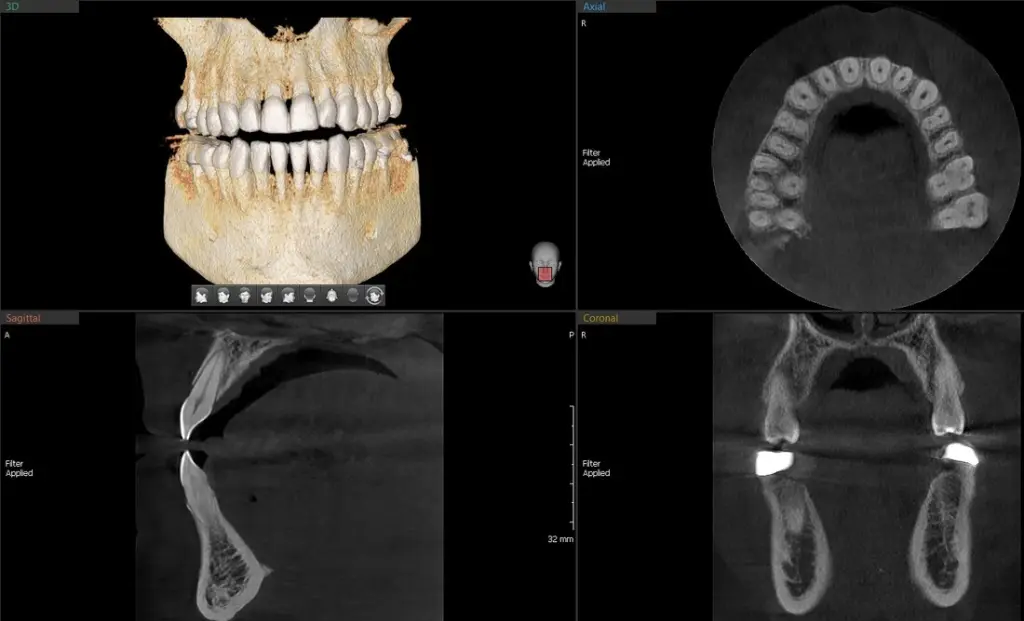

The A9 provides high quality panoramic and CBCT images by combining image processing and accumulated experience in dental imaging from Vatech's image clarity expertise. This will increase your diagnostic accuracy for improved treatment planning and patient satisfaction.

Integral FOV for 3D Image

8x8 (9.3X8 Anatomical) images enable fundamental diagnoses and treatment planning, including both the maxillary and mandibular areas, in a single scan. It is useful for complex implant surgeries and left/right TMJ diagnoses.